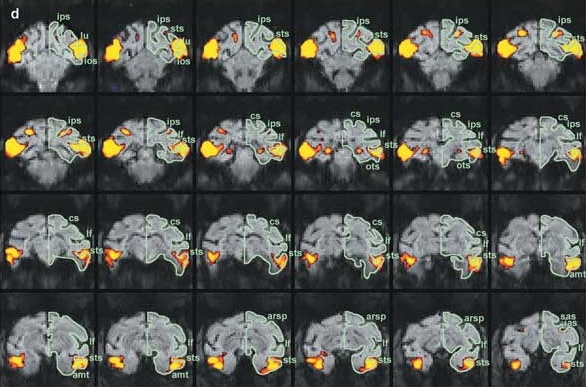

The prize recipients include Nancy Kanwisher, PhD, Winrich Freiwald, PhD, and Doris Ying Tsao, PhD.